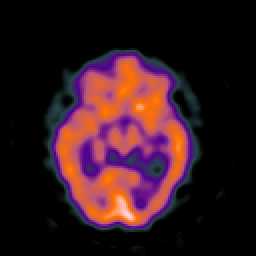

SPECT TC Study #8 -- Slice #24

[Home][Help][Clinical][Tour 1][Tour 2][Tour 3] Slice 24